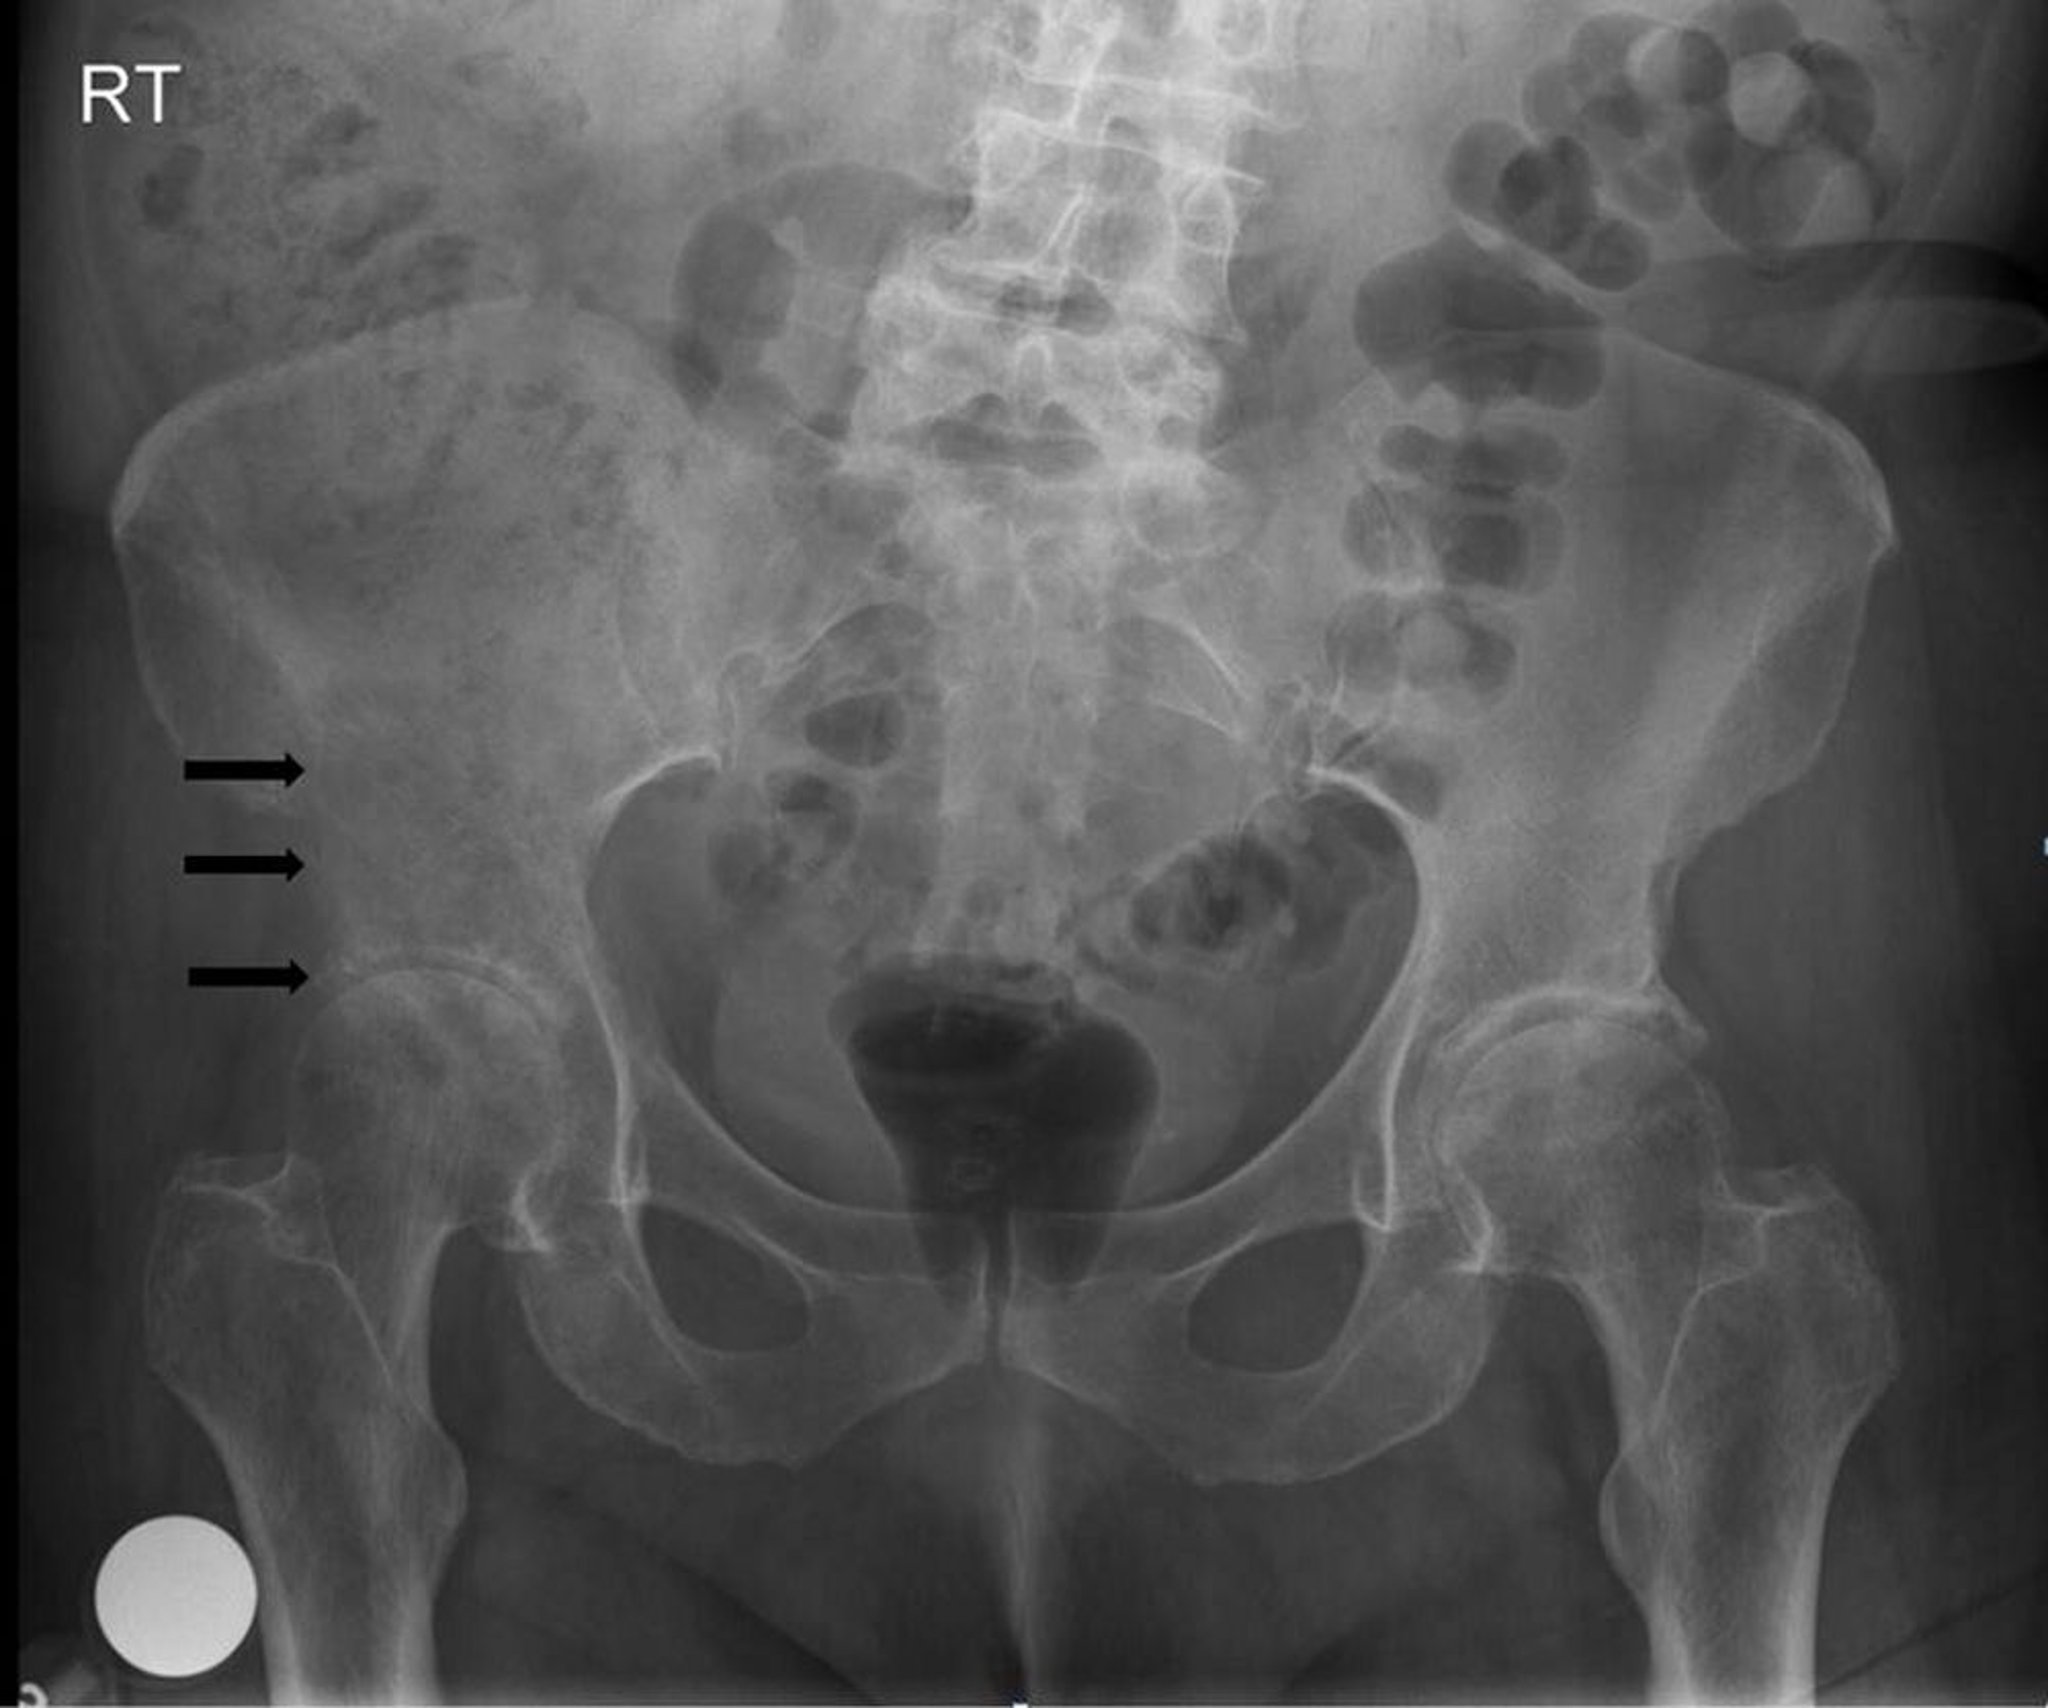

この骨盤のX線前後像では,右寛骨臼およびその上部に融解性の破壊性病変(矢印)がみられ,患者が有する肺癌からの転移に一致する。

Image courtesy of Michael J.Joyce, MD, and Hakan Ilaslan, MD.